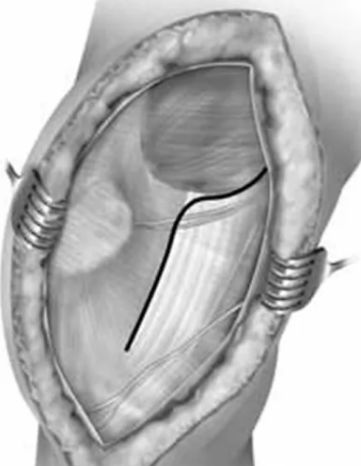

在胫骨结节外侧沿髌骨外侧缘行皮肤切口,延伸至髌骨的外上角,切口长度约12-15cm。

锐性分离膝关节部位皮瓣直至暴露外侧髌韧带,沿髌韧带作梯形手术切口,暴露膝关节,如图1,该切口远端起始于髌腱胫骨止点外侧,沿髌骨边缘的髌韧带延伸至股外侧肌肌腹。

后按一下四个步骤进行股骨远端暴露:1. 使用手指将髌腱从髌后脂肪垫上钝性分离;2. 完全切除髌后脂肪囊和滑囊至半月板韧带水平,注意此时需保护半月板和半月板间韧带;3. 完全松解髌韧带远方胫骨结节止点;4. 最后松解髌韧带上方以获得进入髌上囊的空间。

在胫骨近端靠近内侧半月板水平放置霍夫曼拉钩以牵开髌骨,在髌上囊水平放置另一个霍夫曼拉钩牵开近段股中间肌完成微创swashbuckler入路。

沿髌韧带所作的梯形手术切口,注意该梯形手术切口仍位于髌韧带内而未延伸至股外侧肌腹

微创swashbuckler入路与股骨轴线呈30度角所拍摄的图片。图中整个股骨远端关节面得到接近完整的暴露